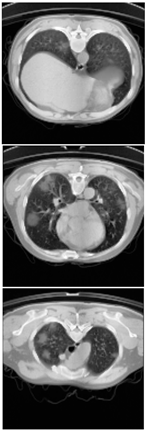

Table 6.

Comparison between ground truth and prediction results of lung segmentation with 3D UNet architecture.

Table 8.

Comparison between ground truth and prediction results of lung and infection segmentation with 3D UNet architecture.